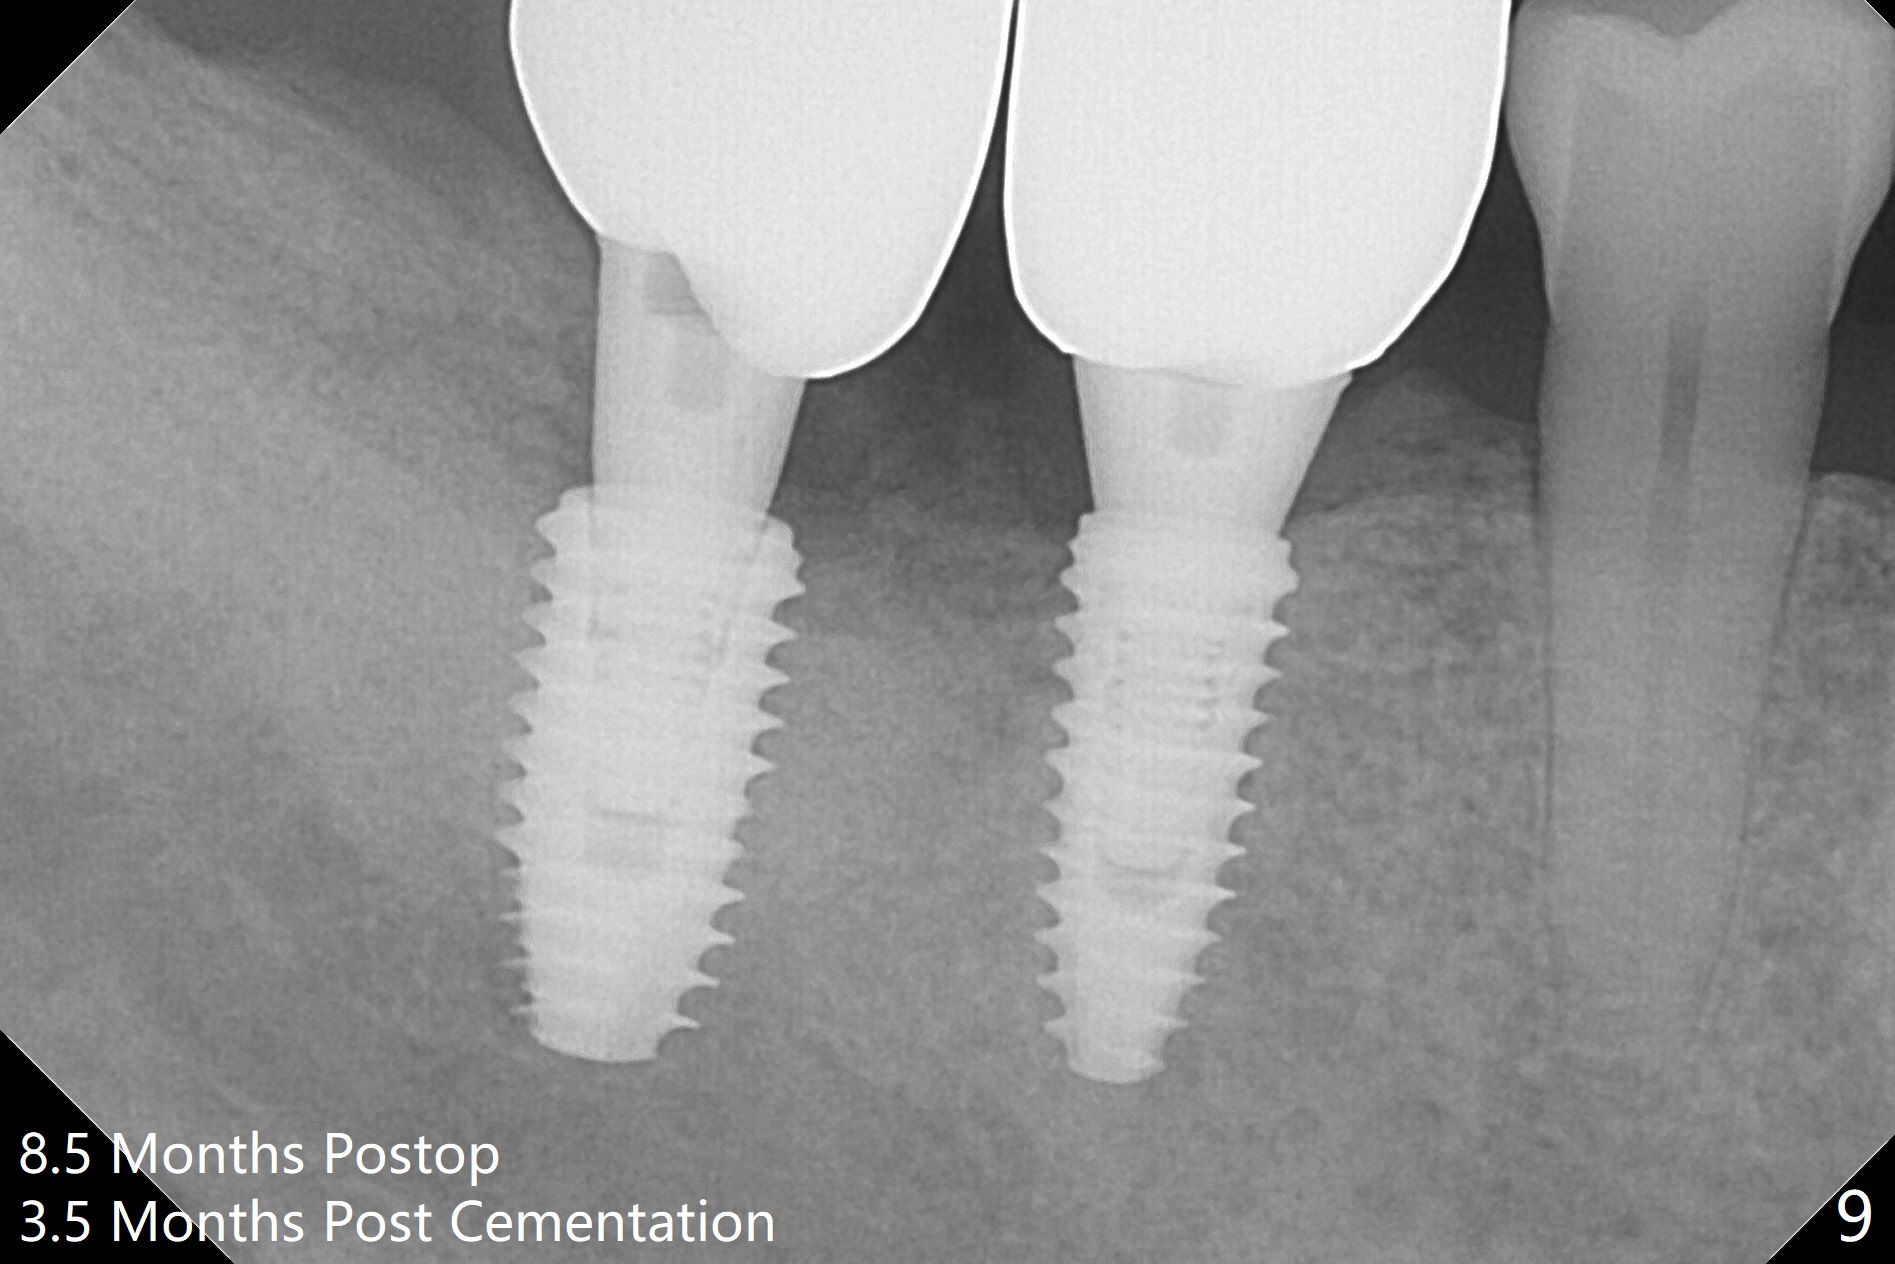

Osteotomy at the sites of #30 and 31 is initiated with Magic Split, followed by Magic Expanders (3.0 and 3.8 mm) at #31. Initial depth of osteotomy is 13 mm with 2.2 mm drill (Fig.1). After adjustment of the trajectory at #31 (Fig.1 arrow) and deepening the osteotomy by 2 mm, dummy implants are placed with stability (Fig.2). Following increase in osteotomy at #31, the larger implant in fact loses stability (Fig.3). The loose implant is pushed distal (Fig.4 arrow) with placement of autogenous bone mesial (*). The stable implant at #30 (Fig.3) and its abutment (Fig.4) are used as a post to hold periodontal dressing, which covers the wound at #31 after placement of collagen plug and suturing. In fact the same technique could be used when socket preservation was performed if an implant were placed at #30 at the same time. When the periodontal dressing dislodges, the wound at #31 heals uneventfully (Fig.5,6). The bone graft seems to remain in place 3 months postop (Fig.7). The implant is uncovered with placement of a 6.8x7 mm healing abutment 4 months postop. When a cementation abutment is placed and prepped, the buccal margin is much lower than the lingual (Fig.8 taken prior to cementation). The patient enjoys mastication with the new implant crowns 3.5 months post cementation (Fig.9).